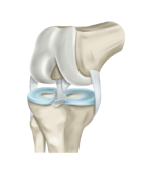

무릎 인공관절 수술 절차는 대략적으로 다음과 같습니다.

- 마취: 환자에게 전신마취나 국소마취를 투여합니다.

- 절개: 피부를 절개하여 무릎 관절에 접근합니다.

- 관절 손상 부분 제거: 무릎 관절의 손상된 부분을 제거하고, 인공 관절을 삽입하기 위한 공간을 만듭니다.

- 인공관절 삽입: 인공 관절을 적절한 크기로 선택하여 무릎 관절에 삽입합니다. 대개 금속, 플라스틱, 세라믹 등으로 만들어진 인공관절을 사용합니다.

- 상처 봉합: 수술이 끝나면 상처를 봉합합니다.

- 치료 및 회복: 치료 과정이 필요하며, 수술 후에는 일정 기간 동안 복원 운동 및 물리치료가 필요합니다.

무릎 인공관절 수술은 일반적으로 국소마취 또는 전신마취로 수행되며, 수술시간은 1시간에서 2시간 정도 소요됩니다. 수술 후에는 병원에서 1~2주 동안 머무르며 치료를 받는 것이 일반적입니다. 그러나 수술적인 위험성과 치료 후에도 부작용이 발생할 수 있으므로, 수술 전에 신중하게 검토하고 진행하는 것이 중요합니다.